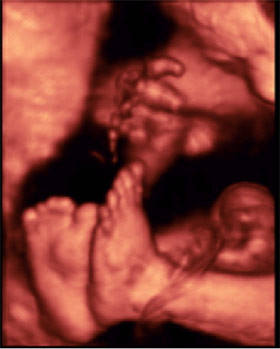

Cómo es un bebé en la semana 32 de embarazo

- El bebé pesa 1.800 gramos y mide unos 42 centímetros de pies a cabeza en la semana 32 de embarazo.

- Todavía el diámetro de la cabeza sigue siendo mayor que el del abdomen, pero el aspecto del feto ya se parece bastante al de un recién nacido.